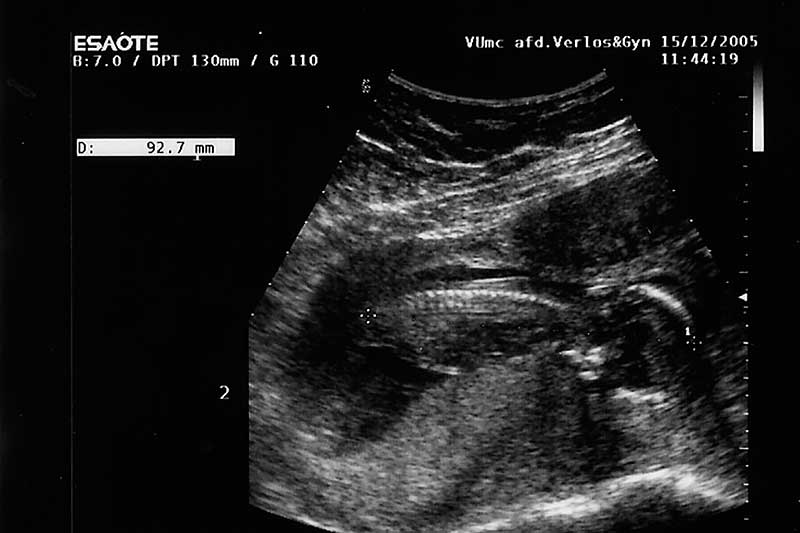

Ik doe de test op zondagochtend, ik zou ongesteld moeten worden maar heb het gevoel dat dat niet gaat gebeuren. Patrick vindt het nog veel te vroeg, maar ik heb er een heel goed gevoel bij. Na al die testen die hieraan vooraf zijn gegaan, na al dat geld dat de firma Clearblue heeft ontvangen van ons, moet dit raak zijn. En dan, dan ben ik zwanger. Gelijk na de eerste keer, een kans van 1 op 5. Alsof deze kindjes perse een Françaises willen zijn. Ja meisjes, zo voelt het meteen. Bij de echo een aantal weken later horen we definitief hoeveel het er zijn. Omdat mijn lichaam door de vele tweelingen in de familie van zowel vaders als moederskant vier eitjes had aangemaakt, zijn we heel benieuwd naar het uiteindelijke aantal. Zonder toegevoegde hormonen toch zoveel eitjes, ook de artsen in het ziekenhuis zijn benieuwd. Twee eitjes zijn aangeslagen, met andere woorden, twee kindjes gaan er groeien in mijn buik.

Na 10 weken begin ik ’s avonds heel erg te bloeden, geen kramp, alleen maar heel veel bloed. We zijn in alle staten en bellen meteen het ziekenhuis. We worden verwacht op de eerste hulp, dus in de auto en scheuren maar. Daar aangekomen moeten we idioot lang wachten, maar als er dan eindelijk na 2,5 uur een echo wordt gemaakt zijn er nog steeds twee hele duidelijke hartjes te zien, alles is goed, er wordt alleen een grote bloedprop weggehaald en we kunnen weer naar huis.

Echo-Mina